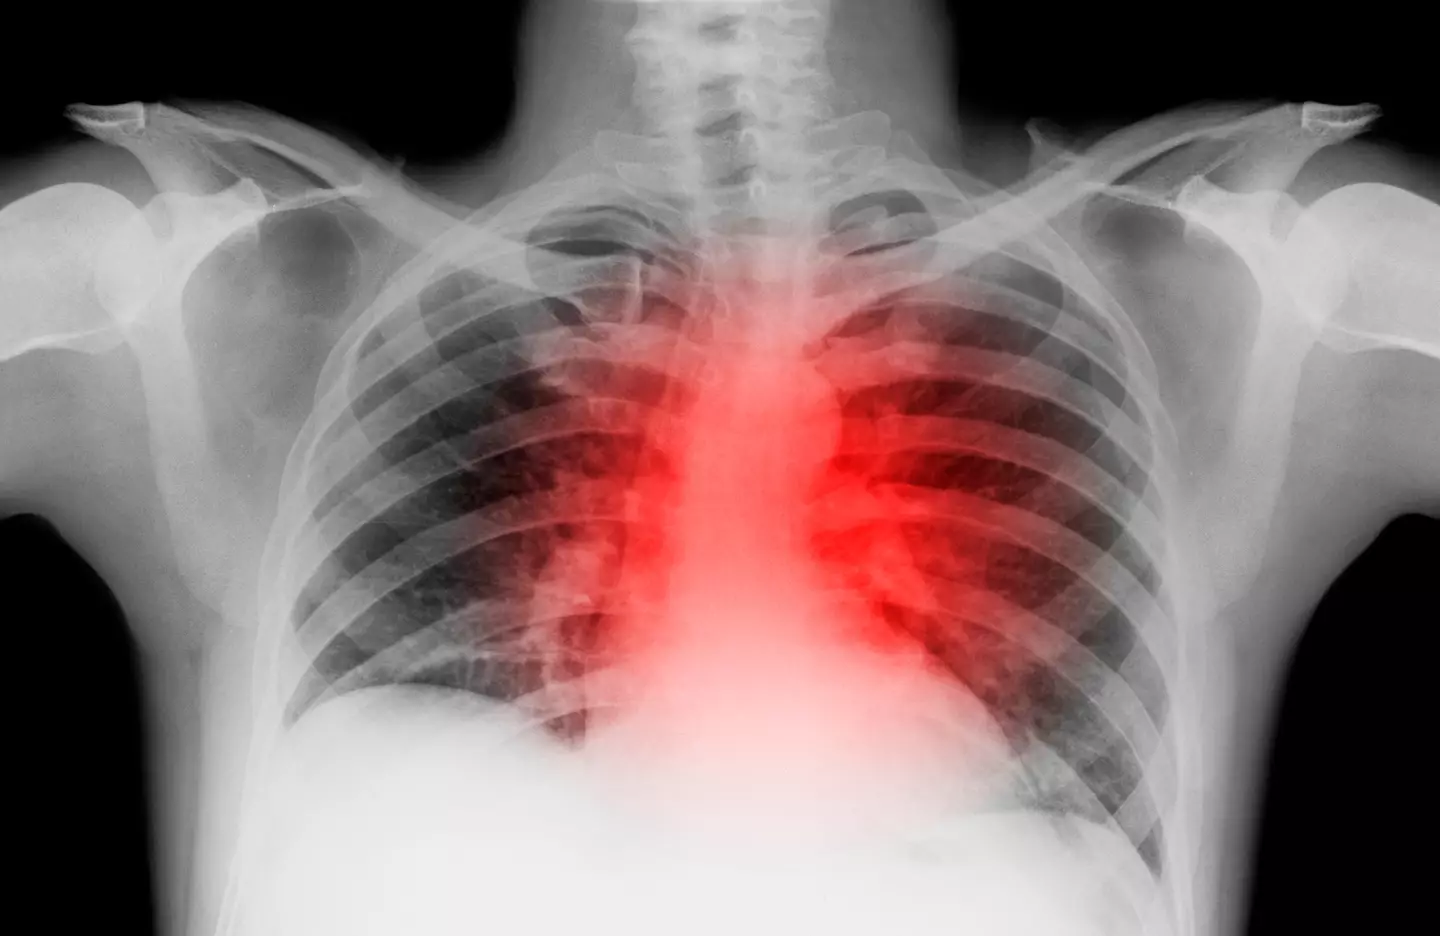

EXPERT SAYS THERE'S ONE MAIN SIGN OF HEART DISEASE EVERYONE SHOULD KNOW

DOCTOR'S WARNING OVER CERTAIN SLEEPING POSITION THAT COULD BE SIGN OF DEADLY HEART FAILURE

According to the NHS, things which can have a negative impact on your heart health include diet, poor blood pressure, smoking and exercise.

It's also important to note the test is also an educated guess and if you have any medical concerns, you should check-in with your GP.